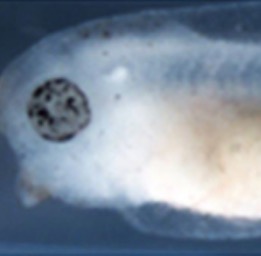

A mutation affecting retinal epithelium identified in the Mill Hill screen for ENU-induced mutations. Splicing mutation in the atp7a copper transporter which results in the deletion of the C-terminal 125 amino acids.Model for Menkes disease. |

Retinal epithelium pigmentation is variegated, melanocytes reduced, head cartilage defects. |

Xtr.atp7a mutant embryos (also known as kaleidoscope /kal) show variegated retinal pigmentation, decreased melanophore number, and head cartilage defects